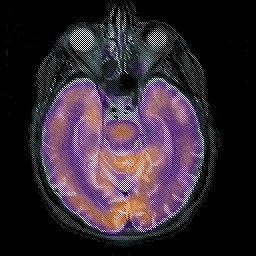

Alzheimer's disease, overlay -- Slice #17

[Home][Help][Clinical][Tour 1][Tour 2] Slice 17